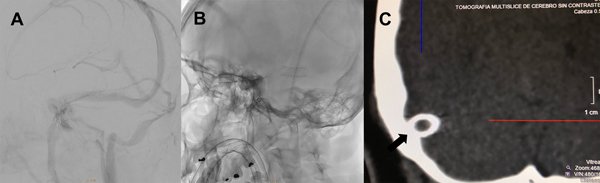

Le indicamos clopidogrel 75mg/día y AAS 100mg/día desde una semana antes del procedimiento. Bajo anestesia general le realizamos un abordaje arterial radial derecho y un abordaje venoso femoral derecho con introductor 5Fr. Se anticoaguló con 10.000 UI de heparina. Bajo guía 0.035 se realizó el recambio del introductor femoral por una vaina carotídea 6Fr progresando la misma hasta el golfo de la yugular derecha. Bajo una guía hidrofílica 0.035 ascendimos un catéter de acceso distal 6Fr hasta el seno sigmoideo derecho (figura 3A). Luego realizamos la angiografía cerebral para determinar el segmento venoso estenosado. Sobre una guía 0.014 localizada en el seno longitudinal superior, bajo roadmap navegamos con técnica rapid exchange un stent balón expandible de cromo-cobalto de 7 por 18mm (Herculink, Abbot) (figura 3B). Una vez localizado el stent a nivel de la estenosis insuflamos el balón con 11 atmósferas hasta llevar el segmento estenosado a diámetros similares a los adyacentes al mismo (figura 3C y 3D). Luego de implantado el stent, realizamos la presurometría del segmento angioplastiado evidenciando un gradiente de presión de 2mm de Hg. Se realizaron todos los controles angiográficos y se retiraron los catéteres arterial y venoso, también se realizó TC de cerebro sin evidencia de complicaciones (figura 4).

La paciente evolucionó con desaparición de la diplopía inmediatamente después de terminado el procedimiento y con desaparición de la cefalea a los 15 días del mismo sin requerimientos de analgésicos y mejoría de la visión. Se otorgó el alta hospitalaria a las 24 horas del procedimiento continuando con doble antiagregación por 3 meses y dando las pautas de alarma. Se realizó un control con angioRM venosa a los 3 meses evidenciando seno transverso derecho sin estenosis (figura 5).

Figura 4: A) Angiografía cerebral digital con adquisición oblicua anterior izquierda en tiempo venoso luego de la impactación del stent en donde se observa el seno transverso derecho sin estenosis residual. B) Radiografía de cráneo en incidencia oblicua anterior izquierda donde se observa el stent abierto implantado en el seno transverso derecho. C) TC de cerebro. Reconstrucción coronal del detalle témporo-occipital derecho. La flecha negra muestra el stent abierto implantado en el seno transverso derecho.

Figura 5: Angioresonancia en tiempo venoso control a tres meses. La flecha blanca señala el seno transverso derecho sin estenosis.